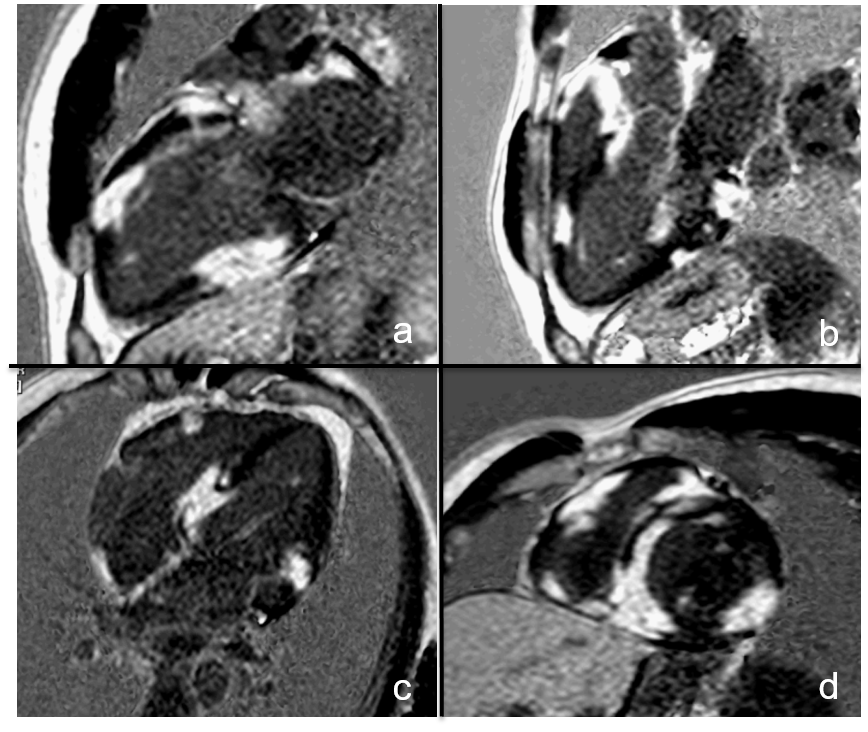

PSIR Imagng (2Ch (a); 3Ch (b); 4Ch (d); SAX (d)). with multifocal and heterogeneous LGE in LV, RV and IAS.